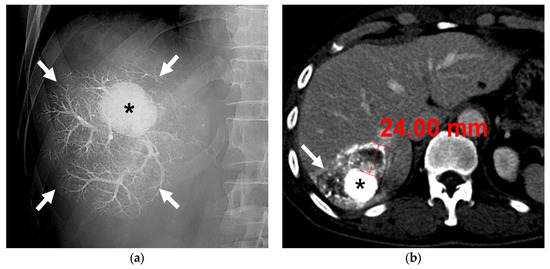

3.1. B-TACE Procedure

3.2. Radiological and Pathological Outcomes